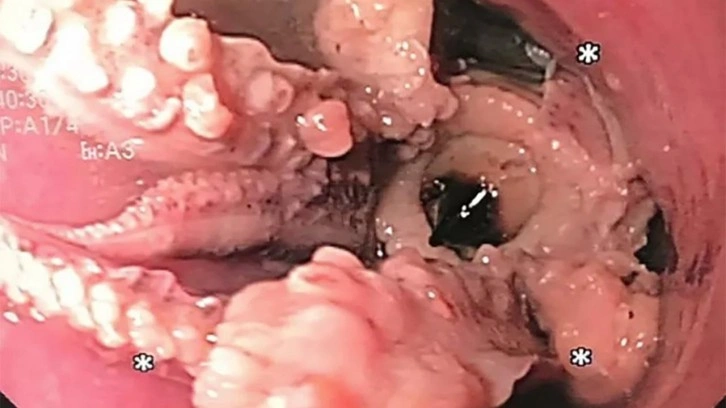

Yemek yedikten sonra yutkunmakta zorlanan bir adam, bunun nedenini öğrenince şok oldu; doktorlar ona, daha önce yediği bir ahtapotun yemek borusuna kaçtığını söyledi.

Singapur’da ismini açıklamak istemeyen bir adam akşam yemeği yedikten sonra sürekli kusma ve boğaz ağrısı şikayetiyle hastaneye başvurdu. Doktorlar yaptıkları tarama sonucunda 55 yaşındaki hastanın yemek borusunda yoğun bir kitlenin olduğunu ortaya çıkarttılar.